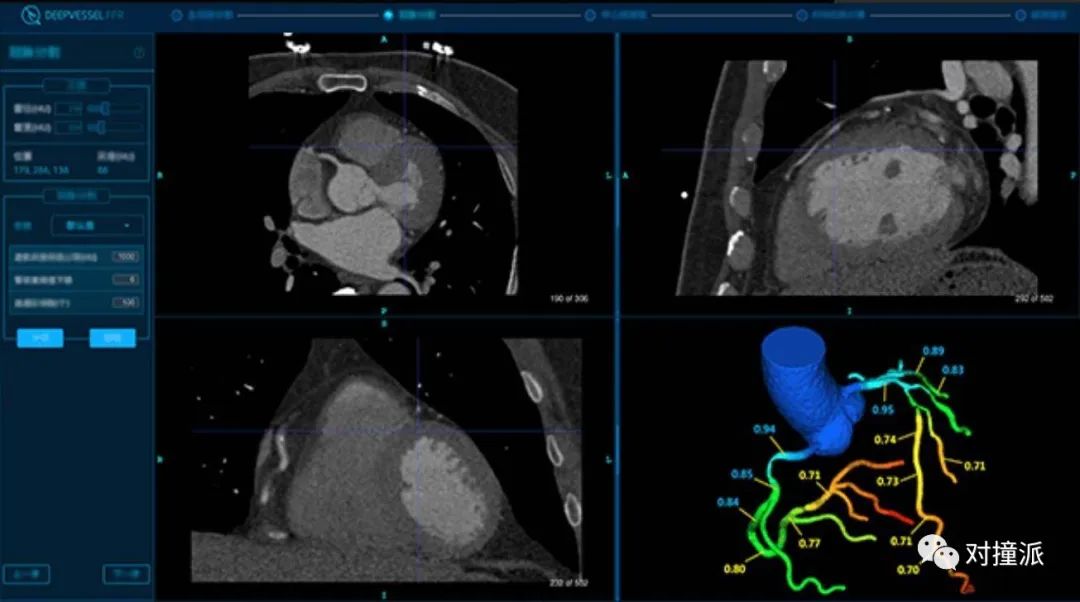

从临床上看,数坤的冠脉CT造影软件、科亚的冠脉血流储备分数计数软件,覆盖的是诊断中紧密相关的两个环节。

在心血管疾病的临床诊断中,CT可以提供详细的解剖学信息,是中低度风险患者的主要排查手段。

医生在通过CT进行初步判断时,血管狭窄情况是重要的量化指标。

“在冠脉诊断里有两个节点,一个是50%,一个是70%,50%以下叫做冠状动脉硬化改变,但不能戴冠心病这个帽子,超过50%会认为是冠状动脉生病了,70%就是考虑介入治疗的指征。”数坤科技副总裁刘建介绍,他曾有过7年影像科工作经验。

与肺部CT不同的是,心血管CT影像,需要医生自己手动将二维图像进行三维重建,还原心脏结果和血管走向分布,再运用电子标尺测量血管狭窄,并进行其它指标的分析。

AI将重建和测量的过程自动化,省去了医生大量重复劳动的精力。这既减轻工作压力,也提高效率,成为了医生日常使用顺手的工具。数坤介绍,目前在北京的安贞医院,医生的软件使用率接近100%。

科亚的冠脉血流储备分数计数软件便是关注在这一应用点。

在目前临床上,血流储备分数(FFR)日益成为重要的量化指标,用来判断冠脉供血情况。2019年发布的《中国冠状动脉血流储备分数测定技术临床路径专家共识》中提到,“FFR已经成为评判冠状动脉缺血的金标准”。

近年来的影像功能学出现的科研热点,则是通过CT手段,运用模拟计算获得FFR,即CT-FFR。关于CT-FFR的临床有效性,近十年来,国外已经进行过多项大型多中心实验。

科亚医疗在2016和2018年分别进行了多中心的实对比实验,将CT-FFR与介入检查得到的FFR结果进行对比。敏感性分别为94.2%,94.7%,特异性分别为84.3%,88.6%。

科亚冠脉血流储备分数计数软件界面